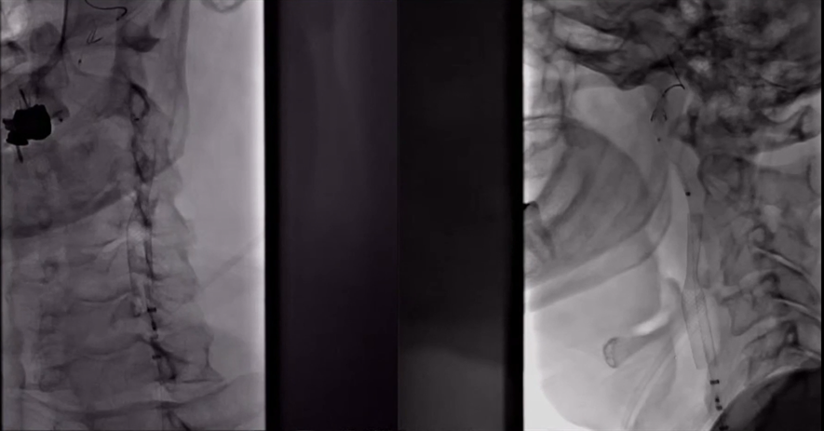

8F Fluxcap®球囊导引导管在5FMPA多功能125cm导管同轴辅助下送至右侧颈总动脉,微导丝送至C4段,沿微导丝送入6mm保护伞至C2段平直段,手推造影显示保护伞打开良好。

沿保护伞导丝送入4.0mm×30mm球囊,充盈球囊导引导管的球囊阻断血流,于狭窄段定位后命名压扩张球囊,泄球囊时在球囊导引导管的体外端予以负压回抽血液,取出一2mm血栓。经Fluxcap®球囊导引导管输送7.0-10.0mm×40mm自膨支架(Protégé RX)至狭窄段确认位置后释放。应用125cm多功能导管回收保护伞,多功能导管体外端予以负压回抽血液,保护伞内有血栓。

造影可见残余狭窄10%左右,颅内各分支血管通畅。

本例患者双侧颈内动脉起始部重度狭窄,右侧颈内动脉为责任血管,故先处理右侧颈内动脉起始部狭窄,避免同期处理双侧颈内动脉起始部重度狭窄增加高灌注的风险。

加奇Fluxcap®球囊导引导管到位顺畅、支撑稳定,充盈球囊可完全阻断近端血流,扩张球囊开始充盈时充盈BGC球囊,采用保护伞和近端球囊双重保护,最大限度地防止扩张时及支架打开时的血栓逃逸,从而降低栓塞风险,提高患者预后。